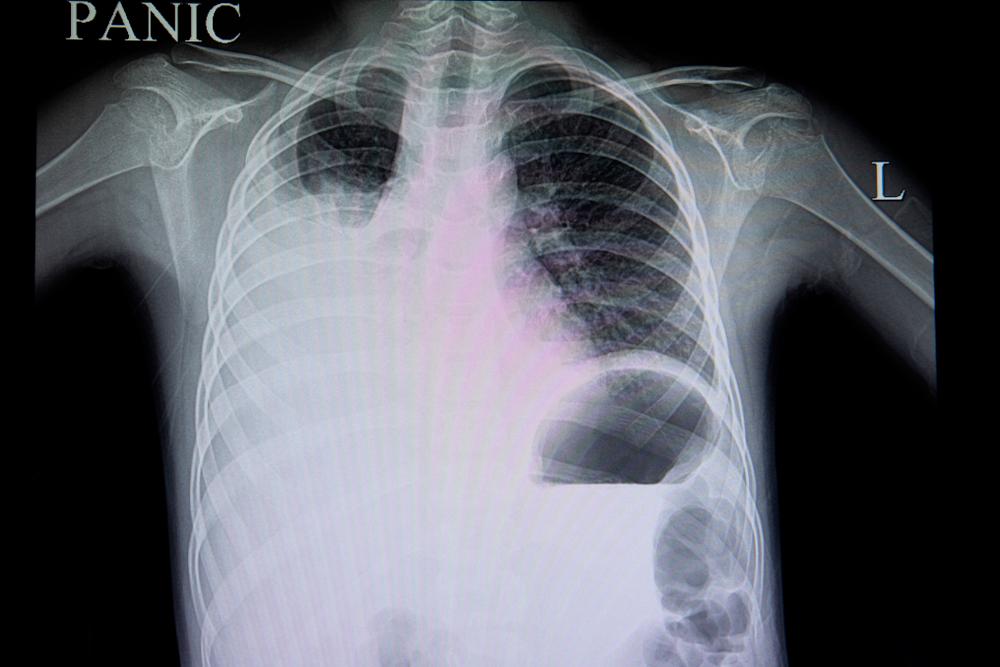

Los signos tienden a desaparecer luego de 7 días, pero si no lo hacen puede ser que el cuadro esté mutando en un caso de dengue hemorrágico (también llamado grave), y aquí es cuando la cosa se complica. Lo que ocurre es que los vasos sanguíneos pueden dañarse, lo que ocasiona la pérdida de sangre. Además, se reduce la cantidad de plaquetas, que son pequeñas porciones sobrantes de la reproducción celular. Ellas tienen un rol central en la coagulación de la sangre. Entonces, la sangre se pierde y encima de todo, tiene dificultades para coagular.

- Respiración anormal.